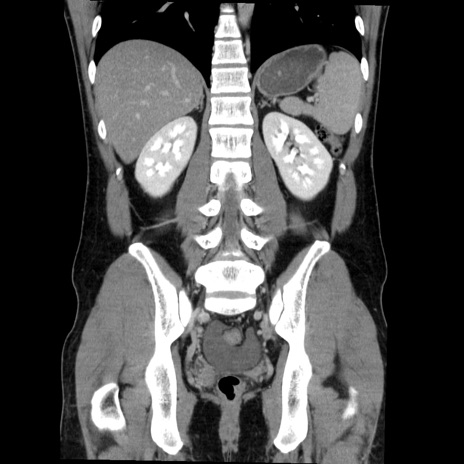

症例36(冠状断像)

【症例】20歳代 男性

【主訴】心窩部痛

【現病歴】今朝より上腹部痛あり。一旦軽快していたが再度出現したため救急要請。昨日夕に白身の魚を含む刺身を食べた。

【身体所見】BP 136/89mmHg、HR 74/min、BT 37.0℃、腹部:膨満、軟、心窩部に圧痛あり。反跳痛なし、筋性防御なし、腸雑音やや亢進あり。

【データ】WBC 17700、CRP 0.48